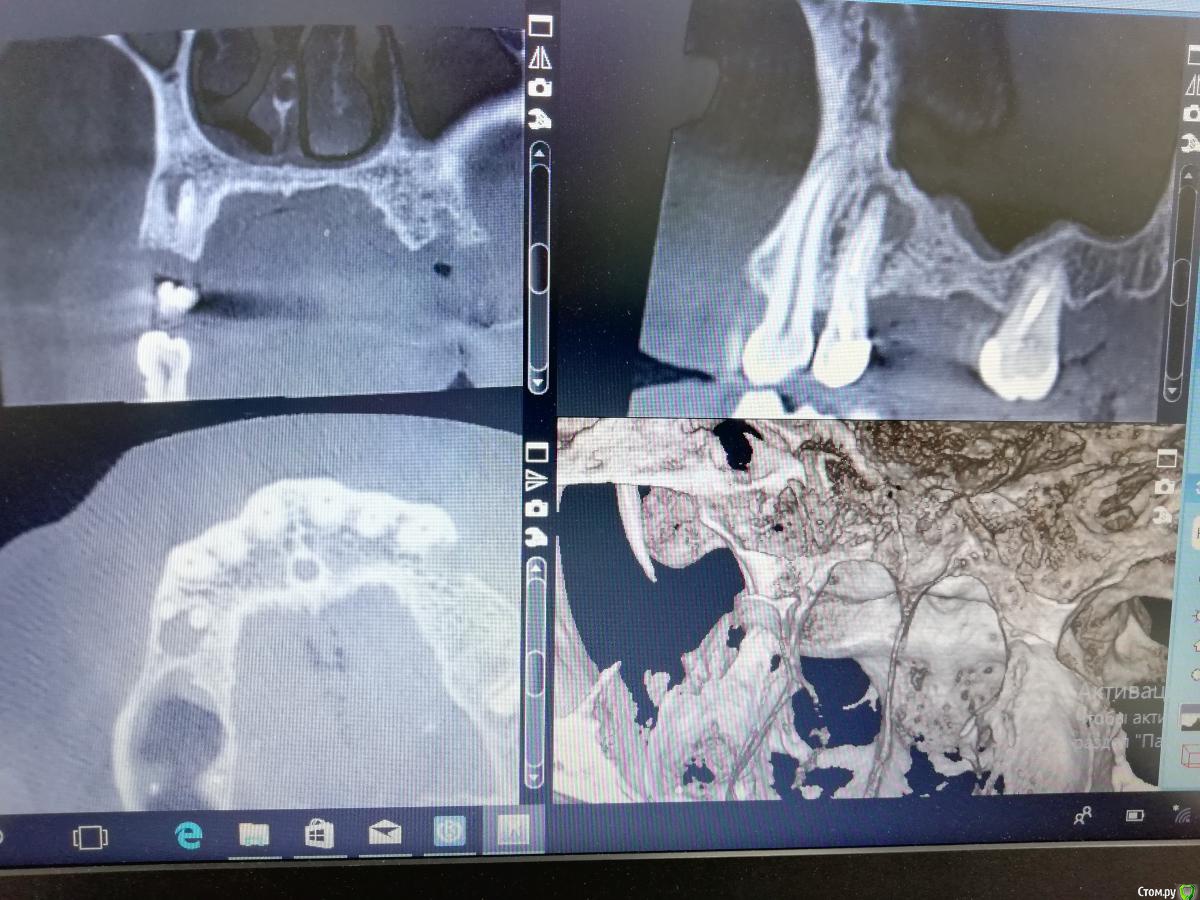

Дмитрий М Опубликовано 7 января, 2020 Поделиться Опубликовано 7 января, 2020 На срезе в первом секторе материал "висит" над костью в пазухе. Что-то нерентгенконтрастное? Во вотором секторе лунка удаленного зуба выглядит пустой. Метериал не вносили?сначала тоже так подумал, но это губка! как я понял ильгамовская)): Ксено +ауто и под них 3 губки на линкомицине (участок с молодыми костными балками без ксено на фото - между графтом и старой границей кости ) 1 Ссылка на комментарий

___49___ Опубликовано 7 января, 2020 Автор Поделиться Опубликовано 7 января, 2020 (изменено) Во вотором секторе лунка удаленного зуба выглядит пустой. Метериал не вносили? Во втором секторе , 27 зуб был удален полсе НКР через 4.5 месяца, лунка (благодаря НКР) теперь имеет все 4 стенки , так как графт был в контакте с зубом 27 (который временно выполнял роль дополнительной стенки) он мог быть обсеменен, свободно лежащие частички графта я убрал и заложил губку на линкомицине - так же максимально желая предотвратить возможное инфицирование графта , но при этом сильно не потерять в кости - чего и добился - фото с расставленными имплантами через 1-2 месяца после удаления 27 го. Что касается губки - она очень хорошо прорастает молодыми сосудами , что играет большое значение в трофике оставшейся кости,а также новой (ксено +ауто) - это сугубо мой личный вывод(не факт что верный) Изменено 7 января, 2020 пользователем ___49___ Ссылка на комментарий